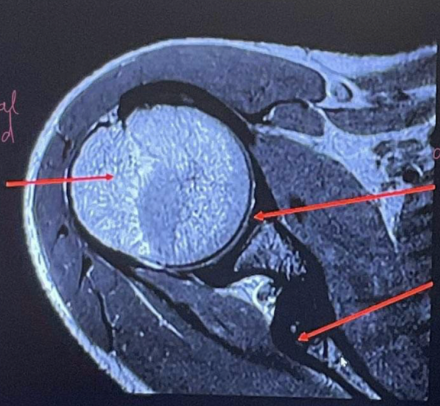

Sequences + why?

T2FS

• Spots of high signal fluid around the humeral head

• Fat is dark hence has been supressed.